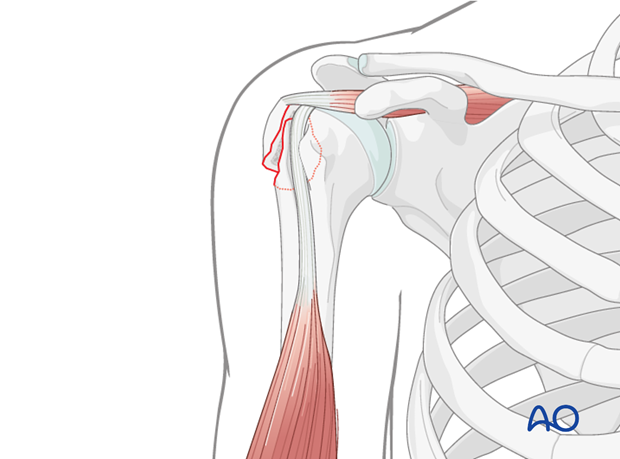

The primary surgical approach for displaced greater tuberosity fractures is typically the deltopectoral approach, offering excellent visualization and broad access. In selected cases, often assisted by arthroscopy, a more limited deltoid-splitting approach may be considered for percutaneous screw placement, but this offers less exposure and increased risk of axillary nerve injury.

- Protecting the Axillary Nerve: Throughout the approach, constant vigilance is required to protect the axillary nerve. It runs roughly 5-7 cm distal to the acromial edge posteriorly. Careful, gentle retraction of the deltoid and avoiding excessive distal dissection are key.

- Identifying the Fracture: The fracture hematoma is evacuated, and the proximal humerus and the displaced greater tuberosity fragment are identified. The fragment is usually retracted superiorly and posteriorly by the supraspinatus and infraspinatus. Inspect the bicipital groove for integrity and position of the long head of the biceps tendon.

This image likely illustrates the initial exposure of the fracture site via the deltopectoral approach, revealing the displaced greater tuberosity fragment.